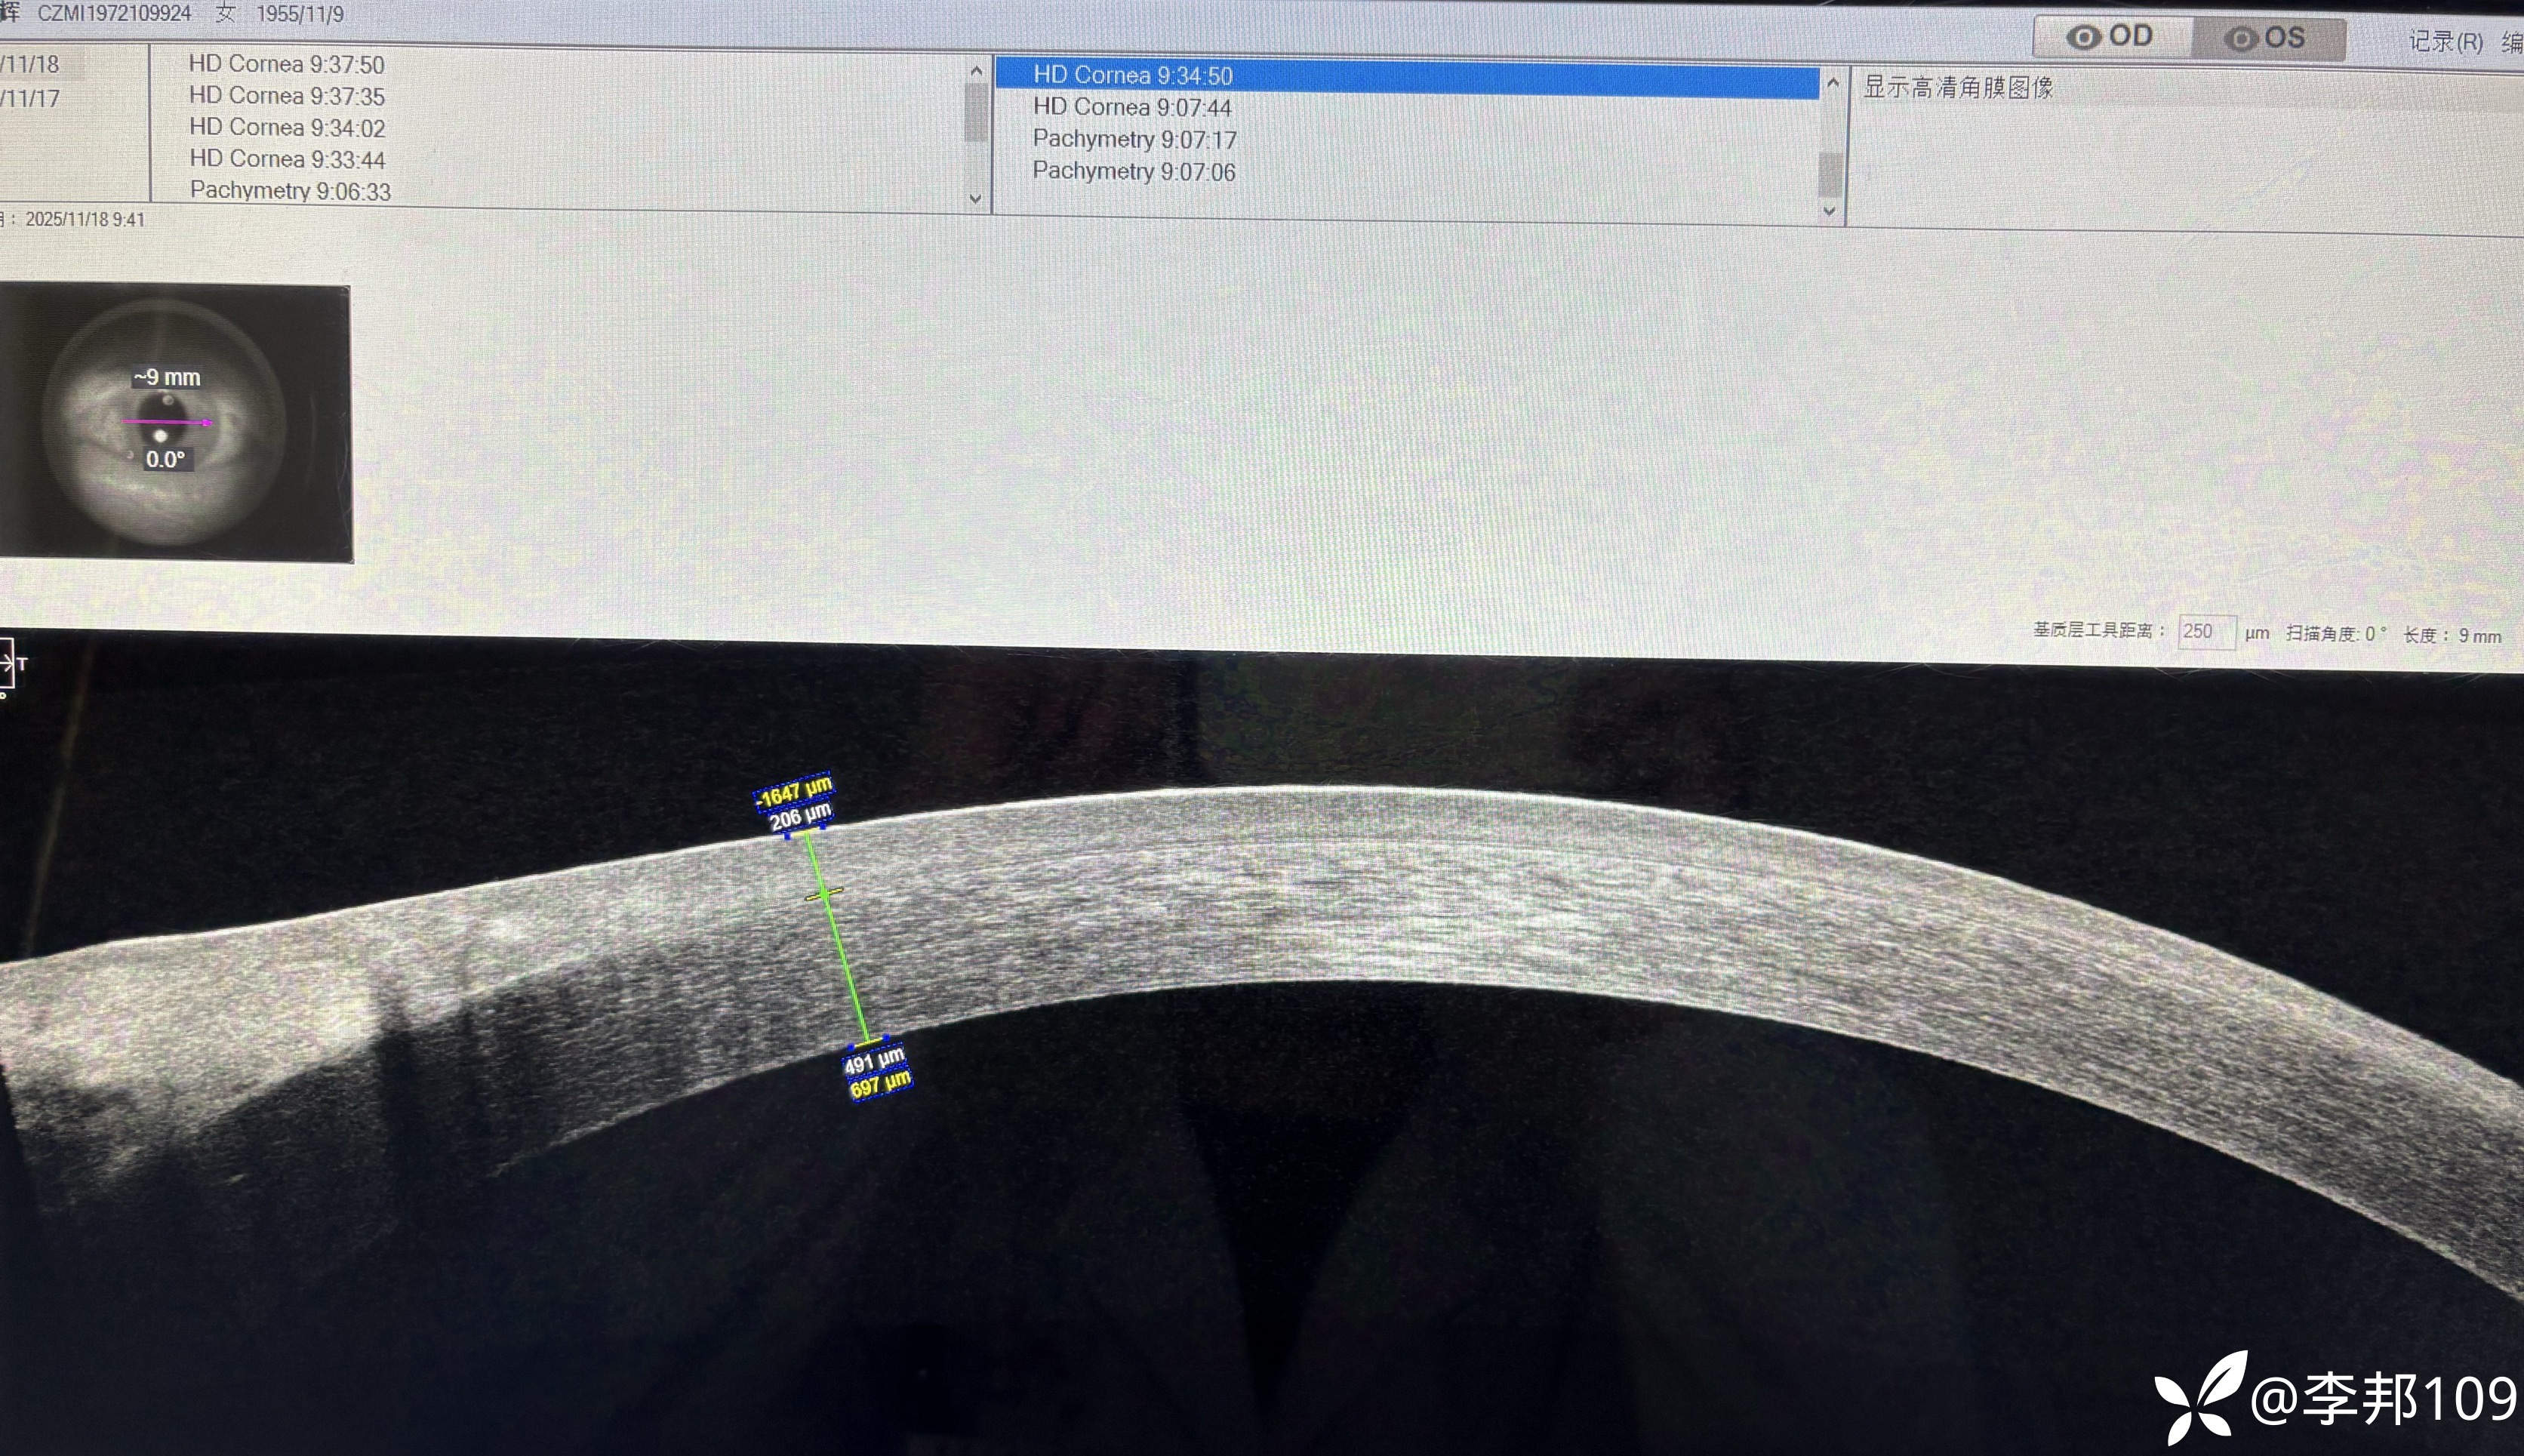

觉得不对劲,做了个AS-OCT,看看“”胬肉“”区的角膜上皮明显增厚

中央的上皮也增厚;颞侧上皮也增厚了